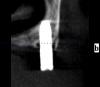

Wasja Опубликовано 10 декабря, 2012 Поделиться Опубликовано 10 декабря, 2012 Вот нарезка КТ Ссылка на комментарий

bullbull Опубликовано 27 марта, 2014 Поделиться Опубликовано 27 марта, 2014 Вот нарезка КТПри хорошем раскладе нижние простоят ещё несколько годков. А на счет верхних - сомневаюсь. Ссылка на комментарий